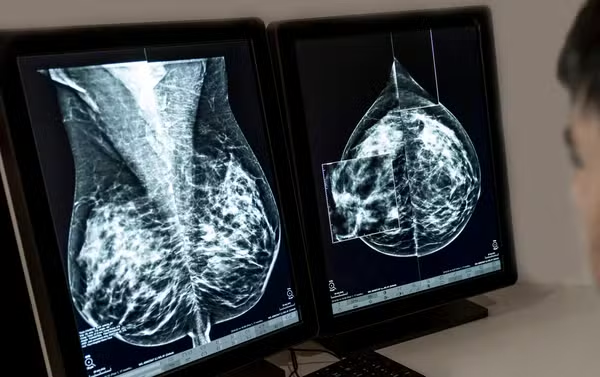

Modelo de inteligência artificial analisa mamografias para avaliar risco do desenvolvimento da doença. Técnica pode ajudar a identificar casos não detectados pelo exame tradicional.

Agora um novo algoritmo promete reorientar a triagem: um modelo de inteligência artificial (IA) consegue avaliar com elevada precisão, simplesmente analisando dados de imagens de mamografia, o risco de uma pessoa desenvolver câncer de mama nos próximos cinco anos.

Por isso, Kuhl defende o rastreamento individualizado do câncer de mama. Afinal, a precisão da mamografia também varia significativamente de mulher para mulher: quanto mais denso o tecido mamário, maior o risco de desenvolver a doença – e pior a identificação pela mamografia. Muitas mulheres não sabem disso, conta a médica.

Ao contrário dos modelos de risco tradicionais, o algoritmo não requer informações sobre histórico familiar, genética ou estilo de vida. Ele calcula a probabilidade de câncer de mama exclusivamente a partir da mamografia e categoriza as mulheres em grupos de risco com base em limiares definidos.

A IA reconhece não apenas a quantidade de tecido glandular, mas também sua textura, o que é outro parâmetro para o risco de câncer de mama. “Apenas cerca de 10% das mulheres têm esse tecido glandular extremamente denso. A grande maioria das que desenvolvem câncer de mama e recebem um diagnóstico tardio têm tecido menos denso”, afirma Kuhl.